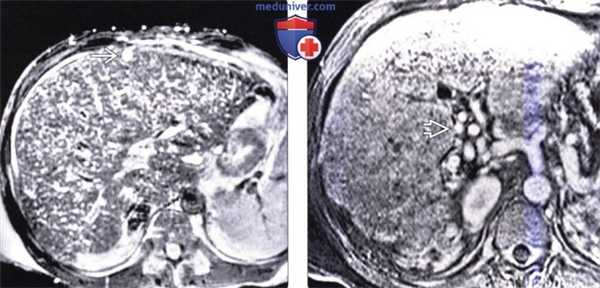

(Слева) На аксиальной КТ без контрастного усиления определяются множественные кисты однородной структуры, низкой плотности, с ровной и тонкой стенкой. Внутренняя структура кист не изменена. В некоторых кистах находится содержимое с плотностью, которая превышает плотность воды, в периферических отделах других кист (в стенке) визуализируются кальцинаты, обусловленные «старым» кровоизлиянием.

(Справа) На аксиальной КТ с контрастным усилением визуализируется увеличенная печень со множественными кистами. Обратите также внимание на кистозные изменения обеих почек. У большинства пациентов поликистоз печени сочетается с аутосомно-доминантной поликистозной болезнью почек.